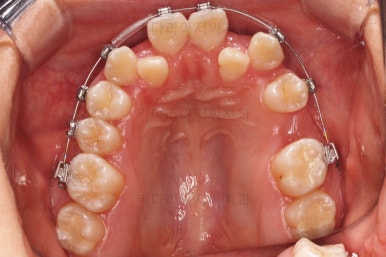

이원교정을 하신지 총 30개월 만에 남아있던 유치 자리가 잘 다물어졌고요.

이 뽑은 자리도 잘 메워졌고, 앞니도 가지런해졌어요.

위아래 치아 갯수도 동일하게 교합도 잘 맞췄고요.

예상보다 빠른 기간 안에 매우 만족스러운 치료였어요.

부산재교정 전후사진을 비교해 볼게요.

치열의 모습이 참 좋아졌고, 입매도 본인이 원하는 수준까지 좋아졌어요.